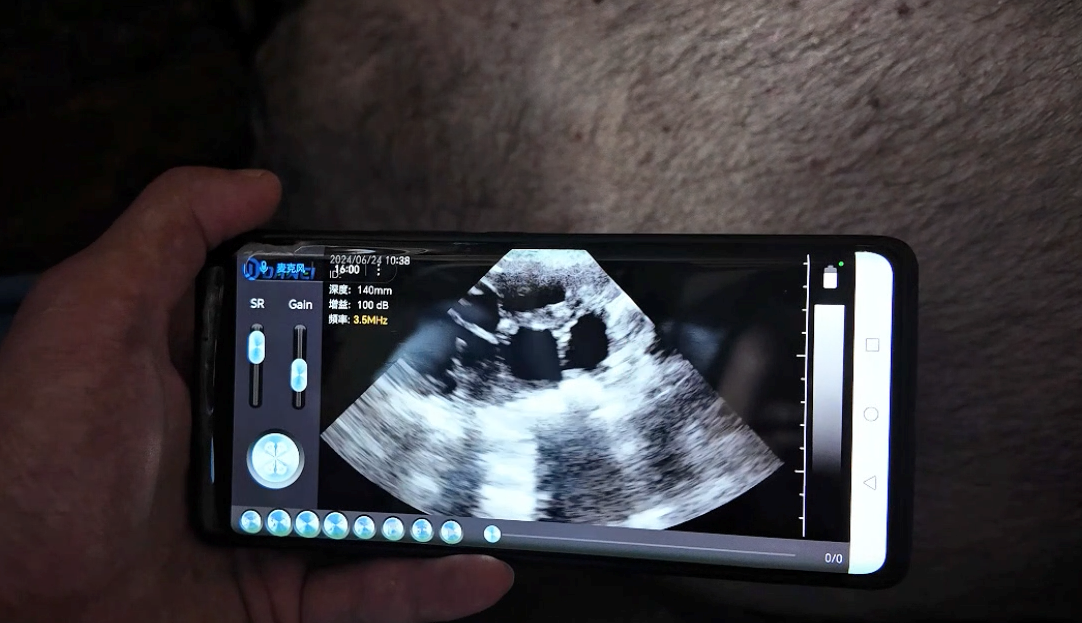

The signs of estrus in sows are sometimes not obvious, and relying solely on behavior observation may lead to misjudgment. By using ultrasound, the morphology of follicles on the ovaries can be clearly observed:

Follicle imaging characteristics: appear as black fluid-filled areas with clear boundaries, gradually enlarging as the estrous cycle progresses;

Approaching ovulation: when the follicle diameter reaches 6–8 mm and the follicle wall becomes thinner, this is the best time for breeding;

Abnormal conditions: if follicles remain unruptured for a long time or cysts appear, ultrasound can promptly identify them and guide intervention.

Around 25 days after insemination, ultrasound can determine pregnancy through the presence of uterine fluid-filled areas and embryonic heartbeats.